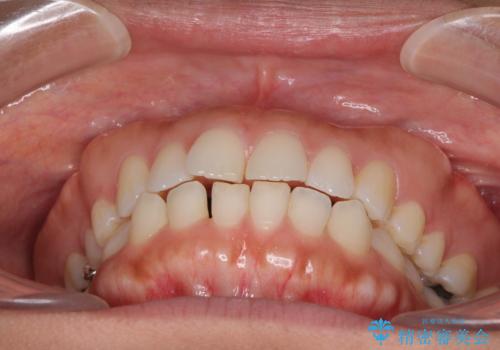

受け口傾向の前歯 すきっ歯の改善

- 前歯の隙間と口元の突出感を気にして来院された患者様です。

嚥下時に舌を突出させる癖があり、成長期に下顎が有意に成長し、歯と歯の間に隙間ができてしまいました。

舌の癖を改善し、インビザラインにて治療を行うこととしました。

舌癖を改善したことで、隙間や突出感を改善することができました。

隙間は後戻りしやすいため、舌側を細いワイヤーで固定することとしました。